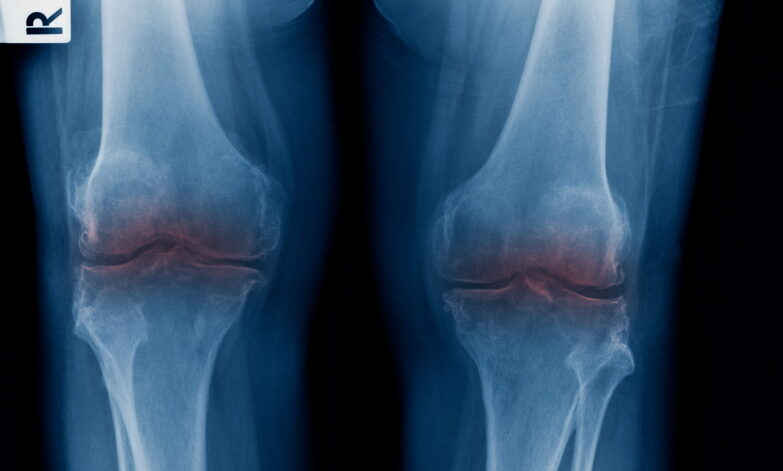

For decades, the medical community has struggled with a fundamental biological hurdle: human cartilage, the slippery tissue that cushions joints, does not heal itself. Unlike skin or bone, it lacks its own blood supply. Once it wears away due to age, injury, or disease, it is gone for goodāleaving patients to endure bone-on-bone friction that leads to agonizing pain and, eventually, invasive joint replacement surgery.

The implications for public health are staggering. Osteoarthritis is a leading cause of disability worldwide, costing the U.S. economy billions of dollars annually in lost productivity and healthcare expenses. Current solutions, such as cortisone shots or physical therapy, offer only temporary relief. Even total knee or hip replacements, while effective, are major surgeries with long recovery times and a finite lifespan of 15 to 20 years.